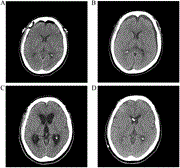

Venous ectasia preceding intra-tumoral hemorrhage in a case of gliosarcoma with transverse sinus involvement

Chaejin Lee and others

Journal of Surgical Case Reports, Volume 2023, Issue 7, July 2023, rjad429, https://doi.org/10.1093/jscr/rjad429